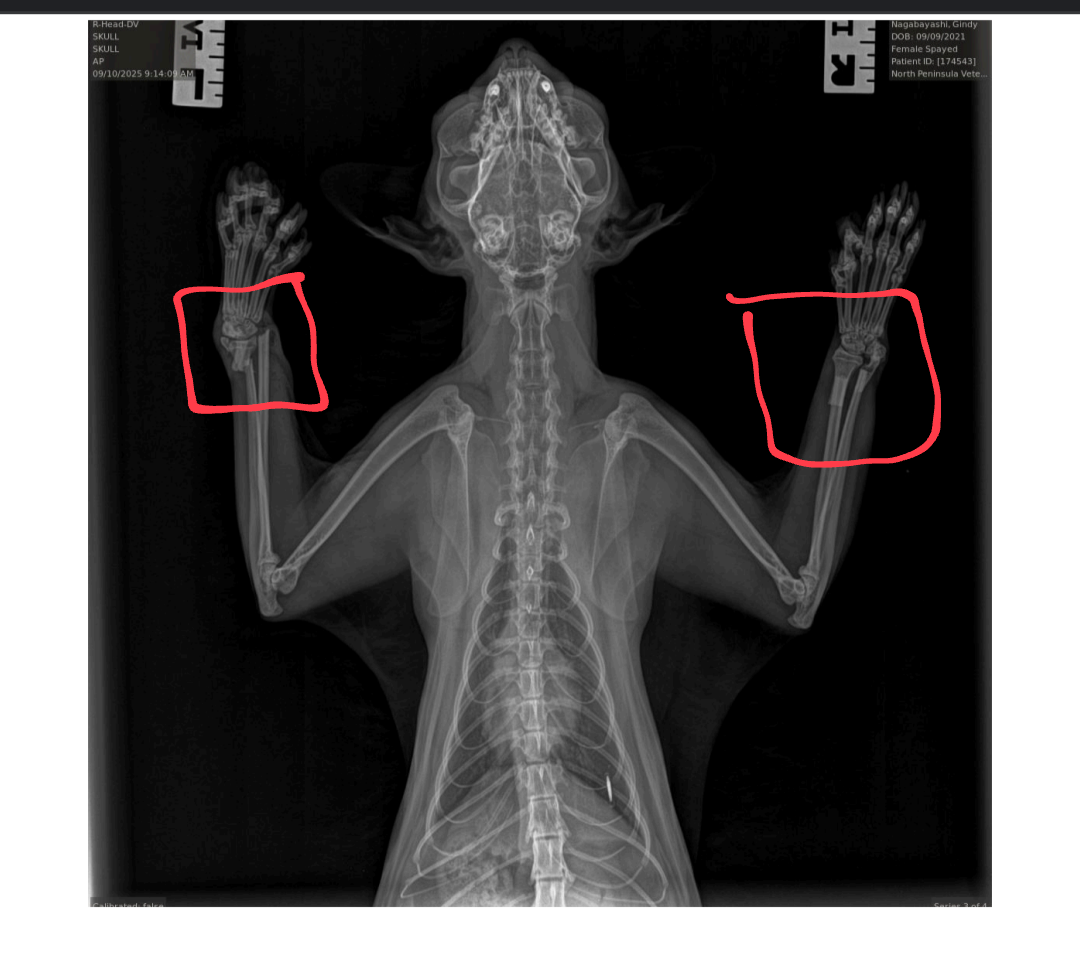

On 09/09/25 Sunny suffered a terrible accident when she fell from a three-story balcony, breaking both of her forelimbs. (X-ray photo shows both limbs fractured).